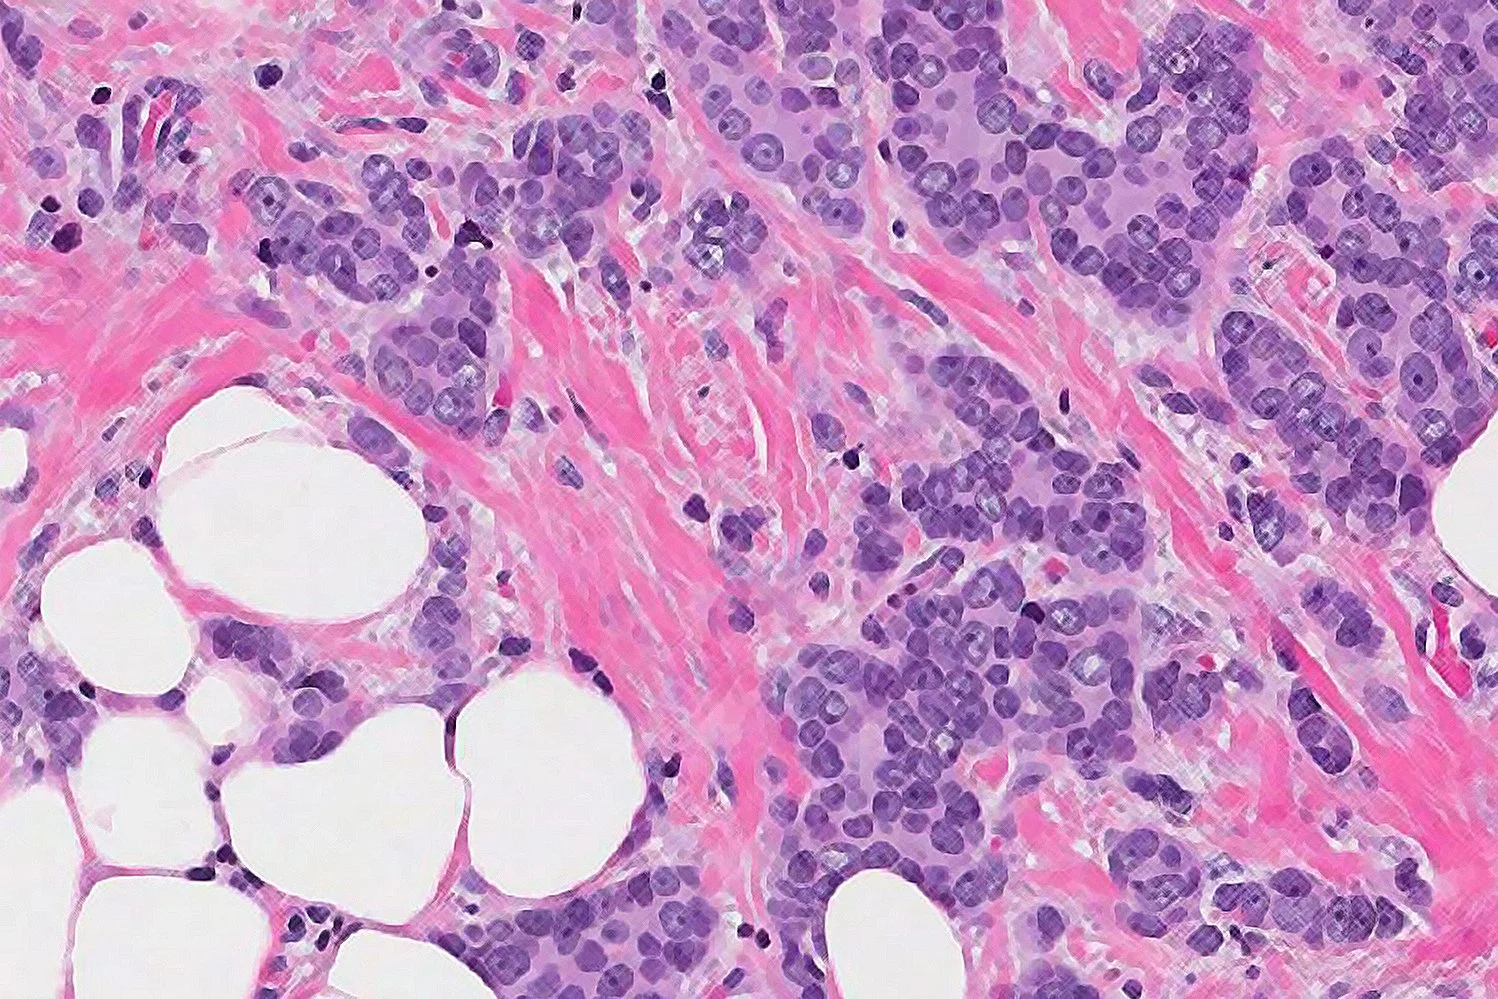

๐ƒ๐ฎ๐œ๐ญ๐š๐š๐ฅ: het zit in de melkgangen van de borst.โฃ

๐‚๐š๐ซ๐œ๐ข๐ง๐จ๐จ๐ฆ: cellen zien eruit als kankercellen onder de microscoop.โฃ

๐ˆ๐ง ๐ฌ๐ข๐ญ๐ฎ: letterlijk โ€œop de plekโ€.โฃโฃ